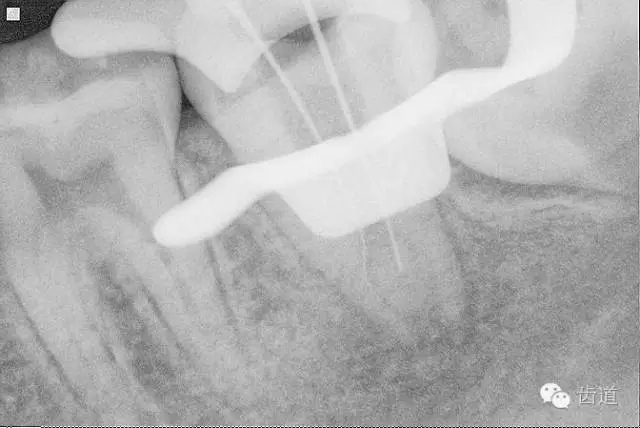

10. X線根尖片示尖 (近中及峽部)

11. 探入近中跟及峽部

17. X線主尖片